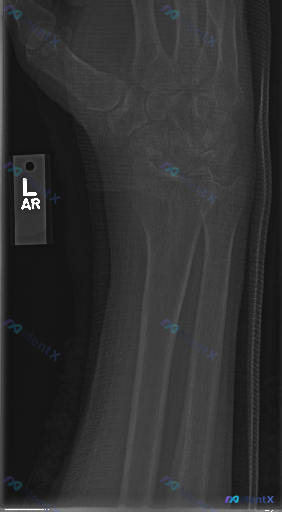

整理到一份左侧腕关节及前臂的正位X光片影像分析资料,想和大家讨论下这种情况的临床思路。 影像基本信息 - 部位:左侧腕关节及前臂远端 - 体位:正位 影像观察到的客观表现 - 骨骼:桡骨远端、尺骨茎突、腕骨(舟骨、月骨等)、掌骨基底部骨皮质连续,未见明显骨折线、错位或骨质崩裂;骨小梁清晰,未见明显骨...